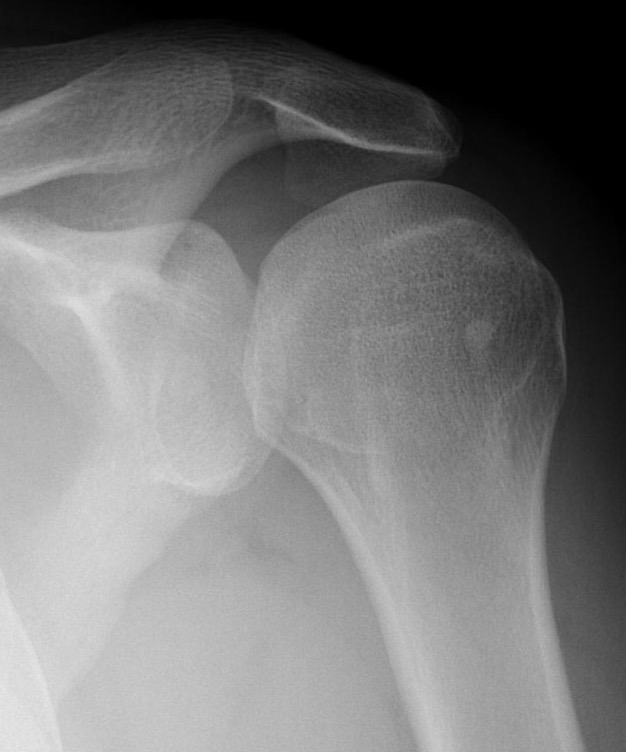

Scapular lateral

Center of the humeral head must be centered on the Y / Mercedes sign

Y is formed by

- coracoid anteriorly

- scapular spine posteriorly

- scapula body inferiorly

Normal scapular lateral

Posterior shoulder dislocation